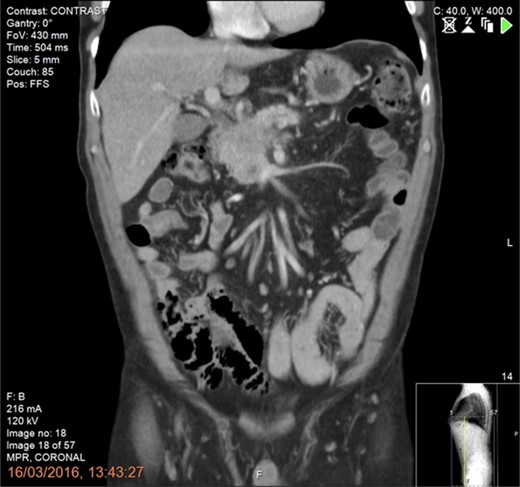

A 61-year-old man diagnosed in January 2016 with a T4N1M0 BRPC in the uncinate process of the pancreas with venous involvement and complete occlusion of the superior mesenteric vein (SMV) and no evidence of metastatic disease (Fig. 1).

CT scan of the abdomen and pelvis (portal phase) demonstrating a borderline resectable pancreatic tumour at the uncinate process with involvement and complete occlusion of the superior mesenteric vein (SMV) and abutment of the superior mesenteric artery.